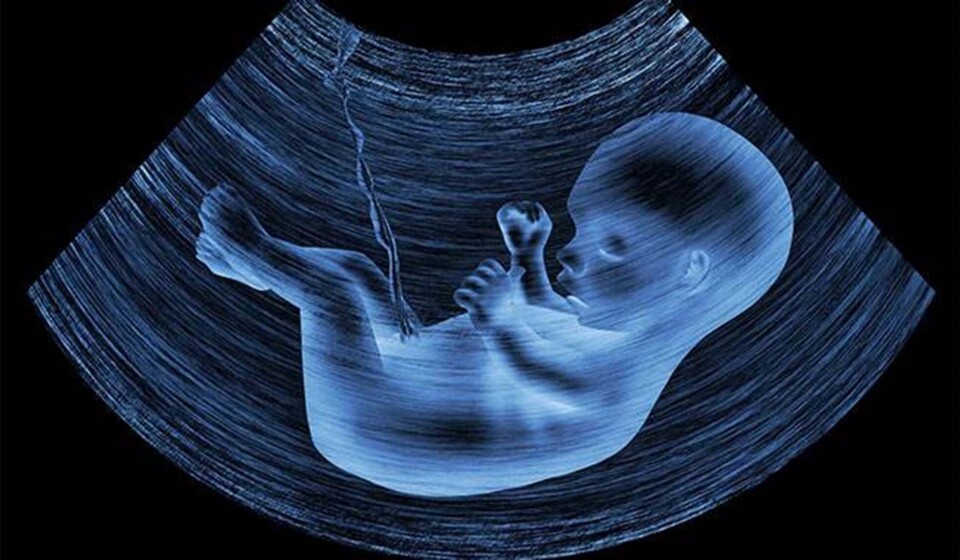

Babyer hører ord inde i maven

Render du rundt med en stor fin mave? Så skal du måske tænke lidt over dit sprog. Babyer kan nemlig høre specifikke ord, før de overhovedet er kommet til verden, viser ny undersøgelse.

Shhh – baby i maven lytter med, når du taler! I hvert fald viser et nyt studie, at babyer kan høre specifikke ord, mens de stadig er i maven, og at de endda husker ordene i dagene efter fødslen.